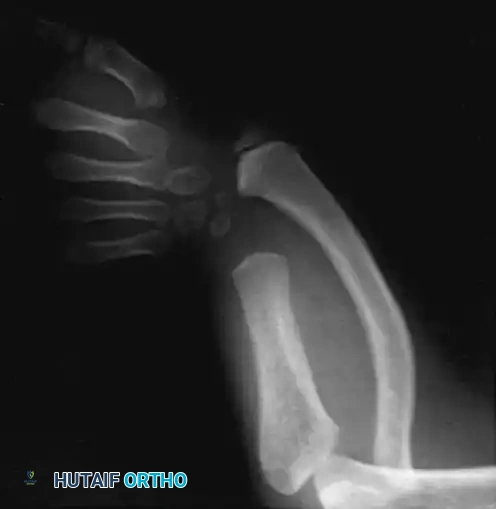

Radiographic Evaluation

Standard orthogonal radiographs usually demonstrate a pathognomonic pattern: an absent distal ulna and a bowed radius with an increased ulnar slope along its distal articular surface.

The pisiform and hamate are typically absent, and coalitions of the remaining carpal bones are frequently observed.